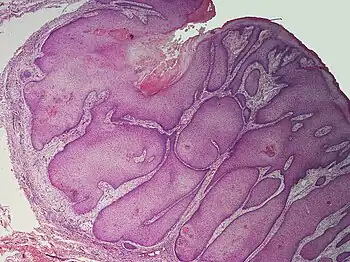

A pilar sheath acanthoma is a single small small or larger bump with a central keratin-plug in a dip, typically above upper lip in adults.[1] It is usually around 05cm to 1.0cm.[1]